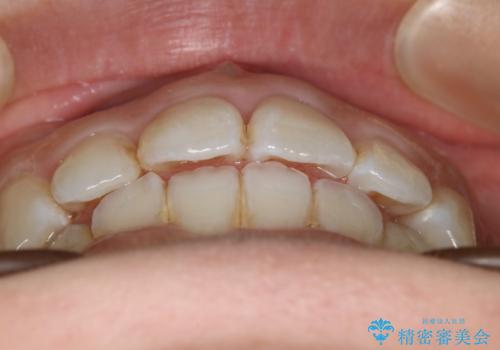

- 歯のガタつきと出っ歯が気になるので矯正治療を希望し来院された患者様です。

上下顎とも歯を並べられるスペースが無く、口元を下げたいというご希望だったので、抜歯とワイヤー矯正を併用した治療を計画しました。

抜歯スペースを利用し口元を大きく下げることが出来ました。